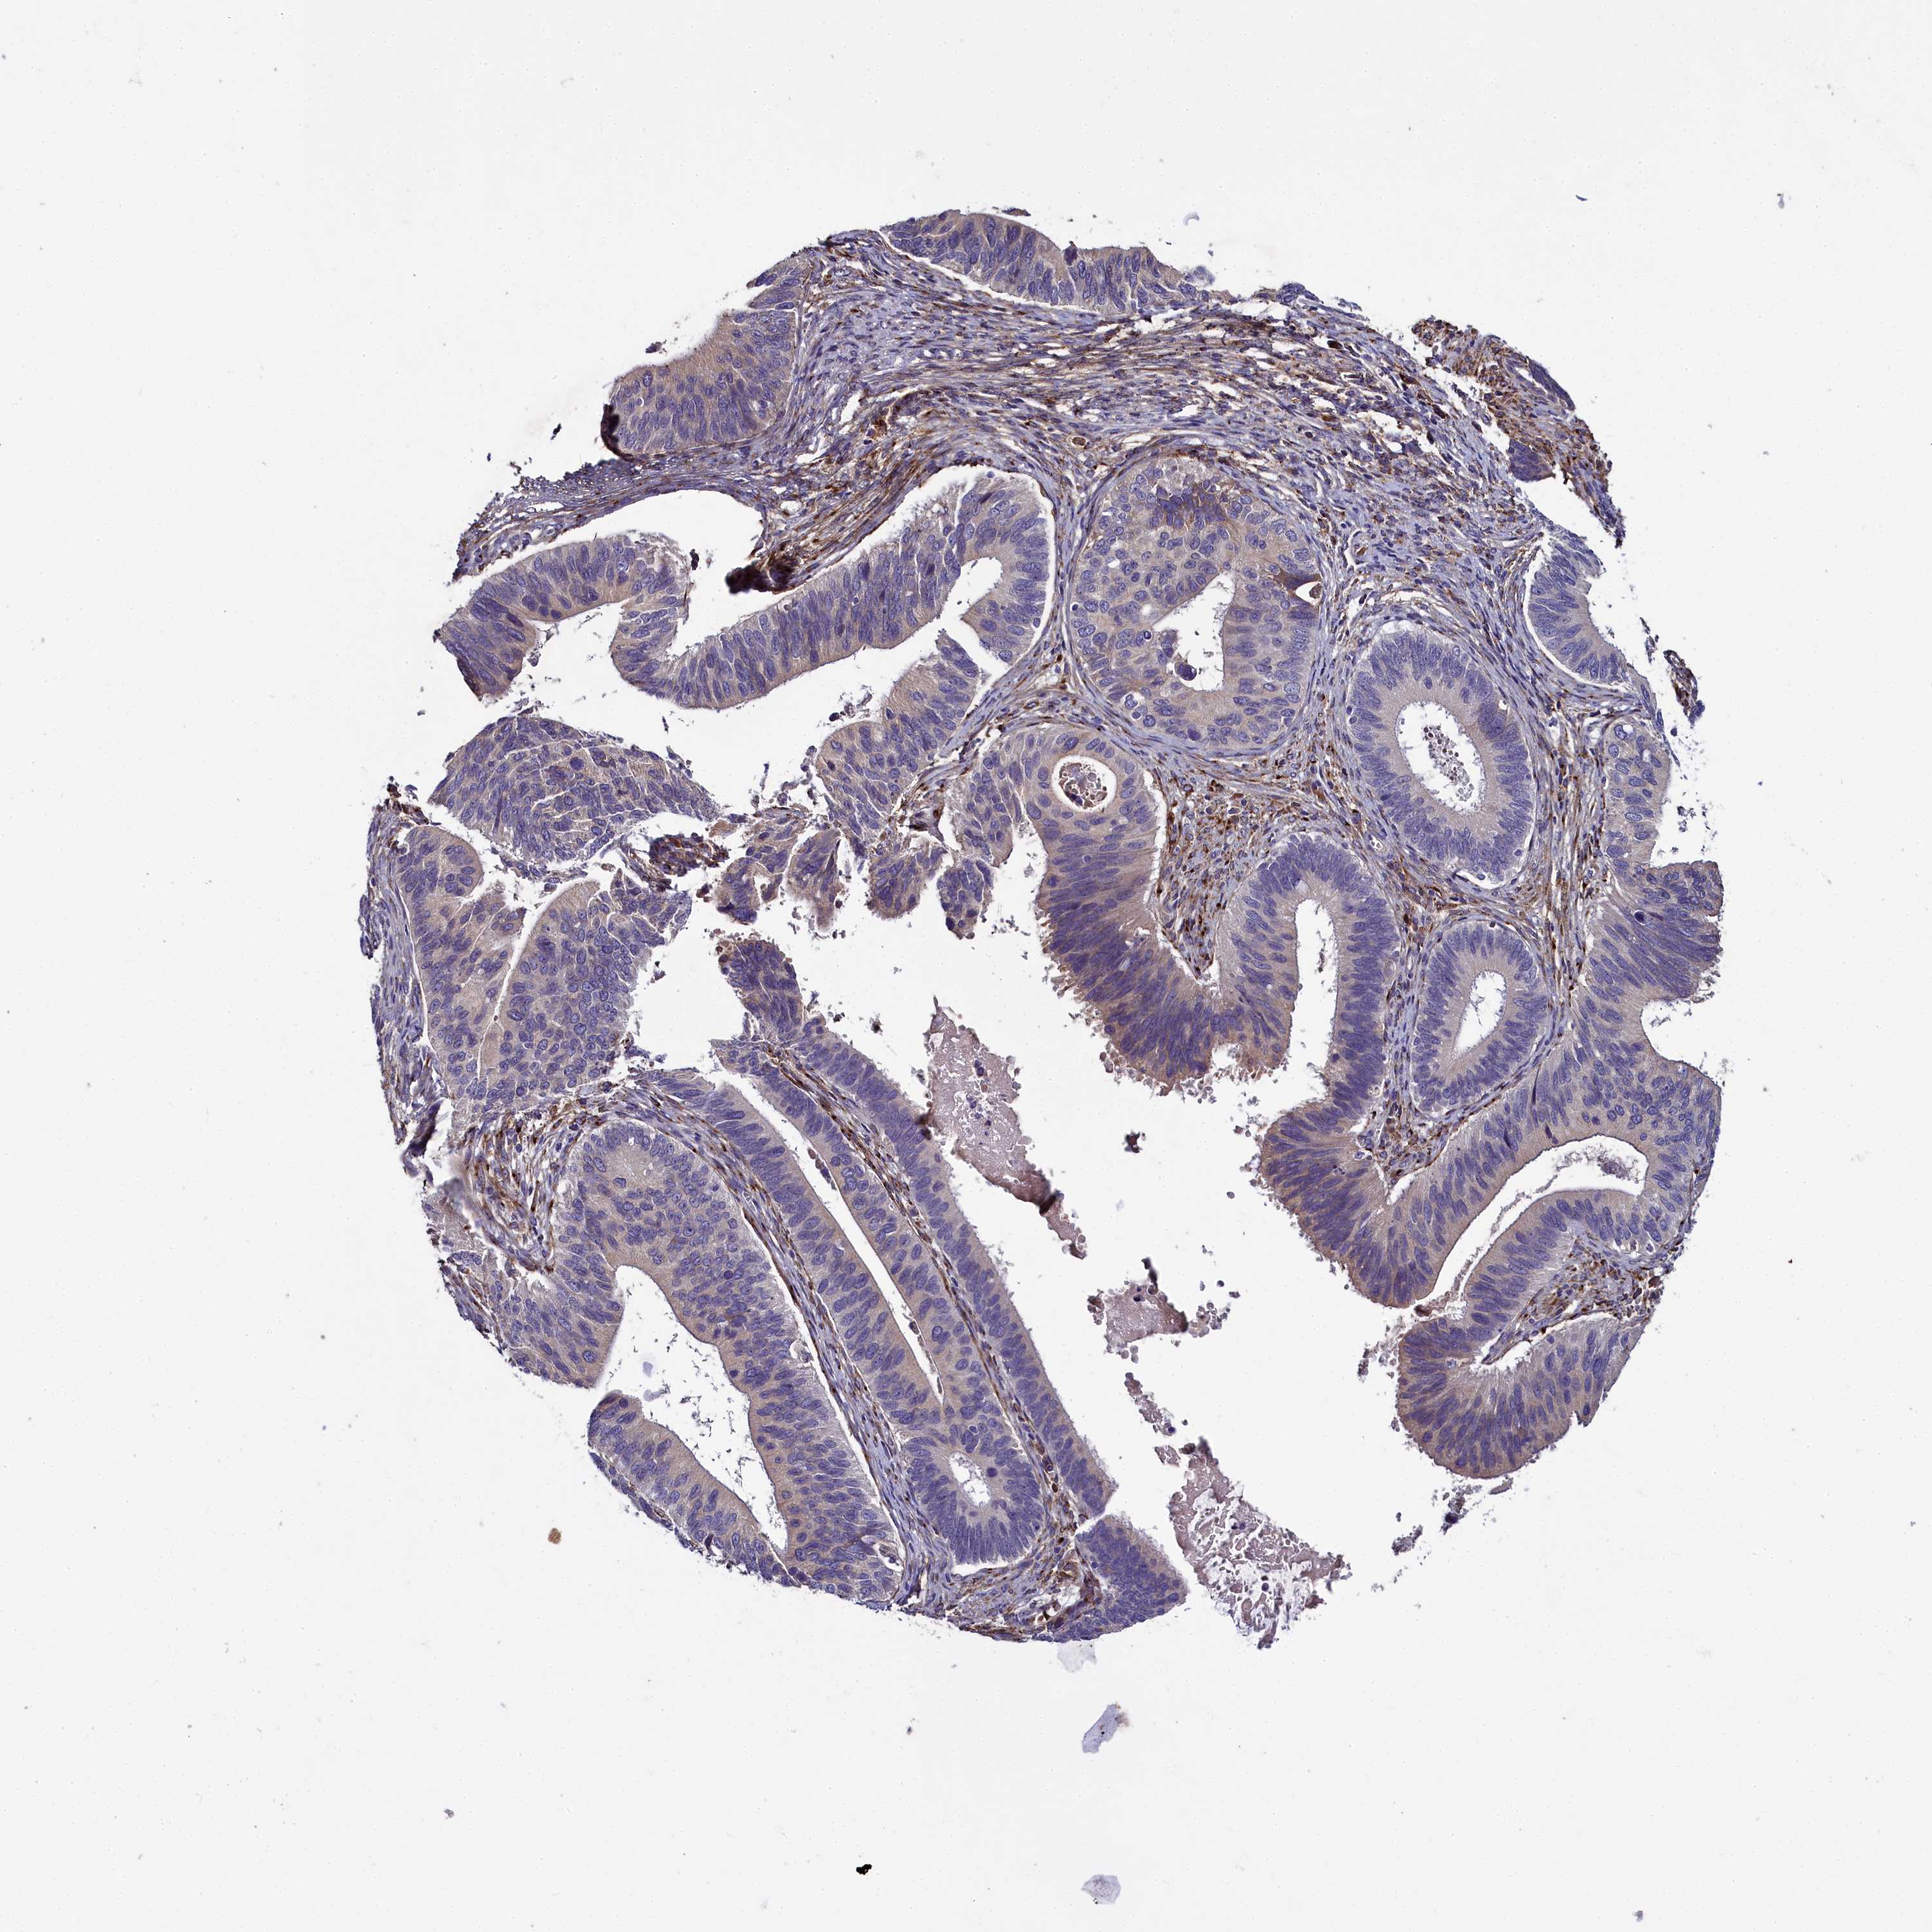

CERVICAL CANCER - Protein expressioni

A mouse-over function shows sample information and annotation data. Click on an image to view it in a full screen mode. Samples can be filtered based on level of antibody staining by selecting one or several of the following categories: high, medium, low and not detected. The assay and annotation is described here.

Note that samples used for immunohistochemistry by the Human Protein Atlas do not correspond to samples in the TCGA dataset.

Antibody stainingi

Antibody staining in the annotated cell types in the current human tissue is reported as not detected, low, medium, or high, based on conventional immunohistochemistry profiling in selected tissues. This score is based on the combination of the staining intensity and fraction of stained cells.

Each image is clickable and will lead to virtual microscopy that enables deeper exploration of all samples and also displays staining intensity scores, fraction scores and subcellular localization as well as patient and tissue information for each sample.

Antibody HPA041991

Staining

Squamous cell carcinoma, NOS

Adenocarcinoma, NOS